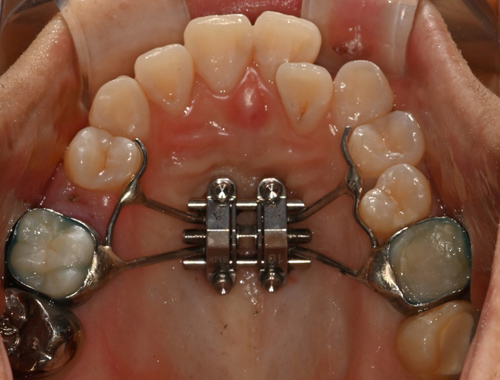

비수술 악궁확장 치료 MARPE (Miniscrew-assisted rapid palatal expansion)

CASE 01

확장 전

확장 후

CASE 02

이지민 원장은 성인 비발치 교정의 핵심인 비수술 악궁 확장 가능성을, 직접 연구한 논문 결과를 바탕으로 사전에 정밀 분석·예측합니다.